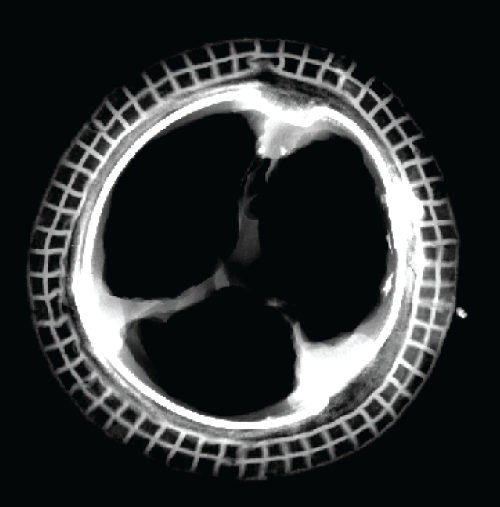

A 58-year-old man had undergone mitral valve replacement with a 27 mm Carpentier-Edwards porcine bioprosthesis (Edwards Lifesciences, Irvine, USA) in 1993. Nineteen years later he presented with dark urine, fatigue and moderate dyspnea denying any history of infection. He was in atrial fibrillation with a systolic mitral regurgitant murmur. Hematologic evaluation was consistent with haemolytic anemia; particularly, reduced hemoglobin, hematocrit and haptoglobin (6.6 mg/dl), and increased total bilirubin and lactic dehydrogenase (752 U/L) with schistocytosis and reticulocytosis were observed. A 2D echocardiogram showed moderate mitral regurgitation and increased pulmonary artery pressure. At reoperation the mitral prosthesis was replaced with a bileaflet mechanical valve. At gross inspection the explant showed pliable leaflets with a small perforation of one cusp; on x-ray calcific spots were detected mainly at one commissure (Figure 1 and Figure 2). The patient recovered uneventfully and was discharged on postoperative day 8 when the haemoglobin hematocrit levels had increased (12.8 g/dl and 37%, respectively), total bilirubin and haptoglobin were normal and lactic dehydrogenase was considerably reduced but still slightly increased (268 U/L).

Figure 1: Gross view of the mitral explant from the atrial (A) and ventricular (B) sides showing perforation of one cusp (arrows)